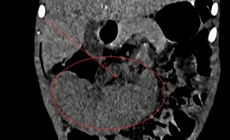

Lần đầu tiên tại Việt Nam phẫu thuật thành công khối phình khổng lồ động mạch thận có ghép thận tự thân

Thành tựu y khoa - 10/10/2025 19:45SKĐS - Bệnh viện TWQĐ 108 mới đây đã điều trị thành công khối phình khổng lồ của động mạch thận ở rốn thận cho nữ bệnh nhân 37 tuổi. Trong quá trình phẫu thuật bệnh viện đã áp dụng kỹ thuật ghép thận tự thân. Đây là ca đầu tiên được thực hiện tại Việt Nam được ghi nhận.